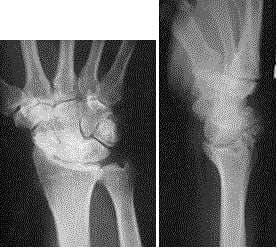

Best Answer: B The clinical presentation is consistent with a SLAC wrist.The radioscaphoid joint is the first to be affected in this process.The radiographs of the right wrist demonstrate a scapholunate dissociation.